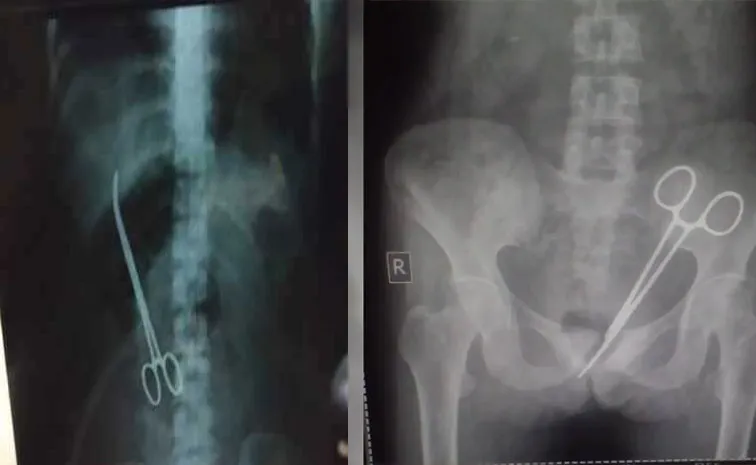

అసలేం జరిగిదంటే.. 45 ఏళ్ల మహిళ 2012లో గాంగ్టక్లోని సర్ థుటోబ్ నామ్గ్యాల్ మెమోరియల్ హాస్పిటల్లో అపెండిక్స్ ఆపరేషన్ చేయించుకుంది. ఈ తరువాత ఊడా ఆమెకు కడుపులో నొప్పి కొనసాగుతూనే ఉంది. చాలా మంది వైద్యులను సంప్రదించి మందులు ఇచ్చినప్పటికీ నొప్పి తగ్గలేదు. తిరిగి వస్తూనే ఉంది. ఇలా పదేళ్లకుపైగా బాధపడుతూనే ఉంది. అక్టోబర్ 8న, ఆమె మళ్లీ ఎస్టీఎన్ఎమ్ ఆసుపత్రికి వెళ్లింది. ఎక్స్-రేలో ఆమె కడుపులో శస్త్రచికిత్స కత్తెర ఉన్నట్లు బయటపడింది. 12 క్రితం అపెండిక్స్ ఆపరేషన్ చేసుకున్న సమయంలో వైద్యులు ఆమె కడపులో ఓ కత్తెరను పెట్టి మర్చిపోయినట్లు తేలింది.

అయితే ఇన్నేళ్లుగా డాక్టర్లు ఆమె కడుపులో కత్తెర ఉందన్న విషయం కనిపెట్టలేకపోవడం గమనార్హం. తాజాగా వైద్య నిపుణుల బృందం వెంటనే మళ్లీ ఆమెకు ఆపరేషన్ చేసి కత్తెరను బయటకు తీశారు. ప్రస్తుతం ఆ మహిళ ఆరోగ్యం నిలకడగా ఉందని, కోలుకుంటున్నారని వైద్యులు తెలిపారు. అయితే విషయం బయటకు పొక్కడంతో ఆ రాష్ట్ర వైద్యఆరోగ్య శాఖ.. హాస్పిటల్ సిబ్బందిపై ఆగ్రహం వ్యక్తం చేసింది.